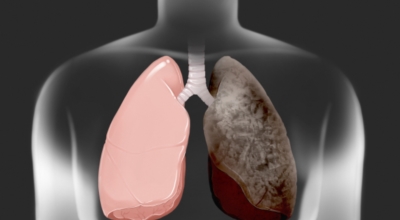

폐에 발생된 악성 종양을 말하며 오랜 기간 흡연해온 남성들에서 발병률이 높고 요즘 들어서 갖가지 환경적인 요인의 영향과 간접흡연으로 흡연하지 않는 여성에서도 많이 발생하고 있답니다. 증상을 느껴 병원을 찾았을 때는 수술하기 늦은 경우가 많아 사망하는 비율이 매우 높은 암입니다. 폐 자체에서 생기거나 다른 장기에서 발생된 암이 폐로 전이되어 나타나기도 하고 특별한 초기 증상이 없는 경우가 많으며 암이 진행된 후에도 일반적인 감기 증상인 기침과 가래 외의 특이 증상이 나타나지않아 증상만으로는 진단이 쉽지 않아요.

폐암의 공통 위험요소로 손꼽히는 이유가 되는 것으로 흡연이 있답니다. 흡연자는 비흡연자에 비교해 십몇 배는 더 폐암 발병확률이 높다고 하며 어느정도 기간 동안 흡연했는지에 따라 폐암 발생확률은 더더욱 더 높아져요. 흡연자라고 해도 금연을 하게 되면 폐암 발병확률이 빠르게 내려간다고 하니 폐암이 걱정되신다면 가장 먼저 금연은 필수입니다.